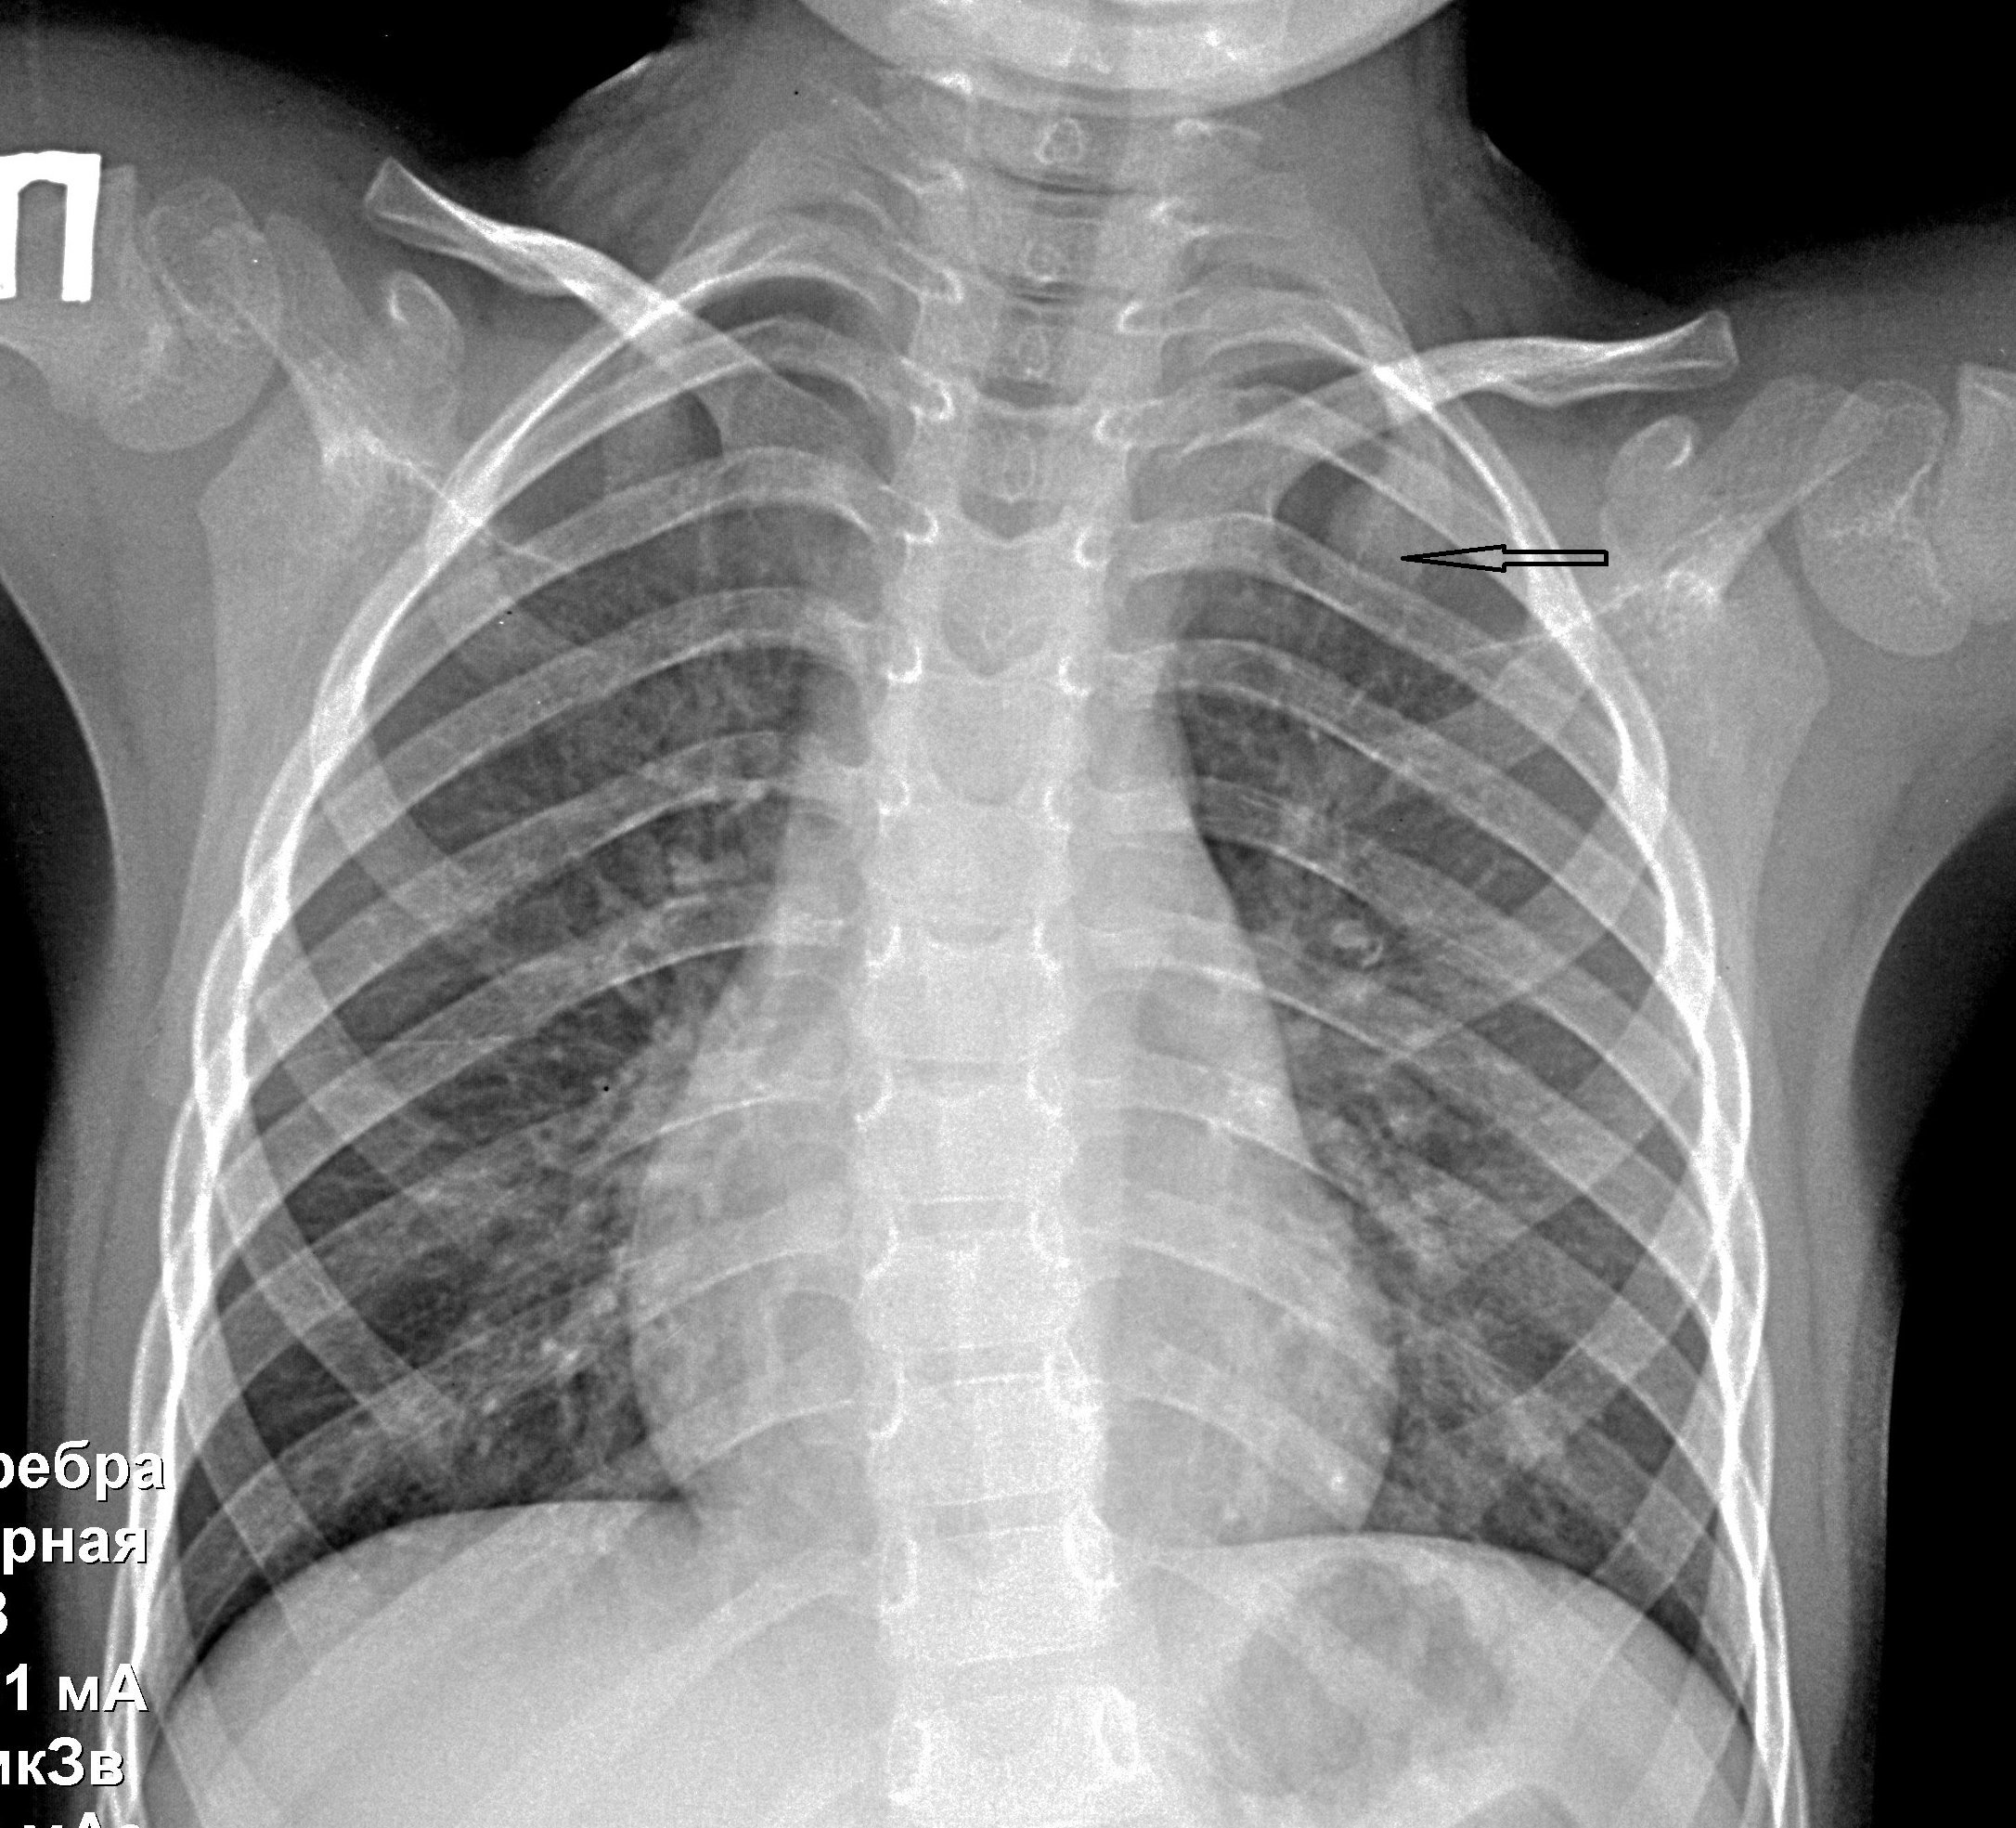

Медицина и диагностика: Аномалии ребер на рентгене